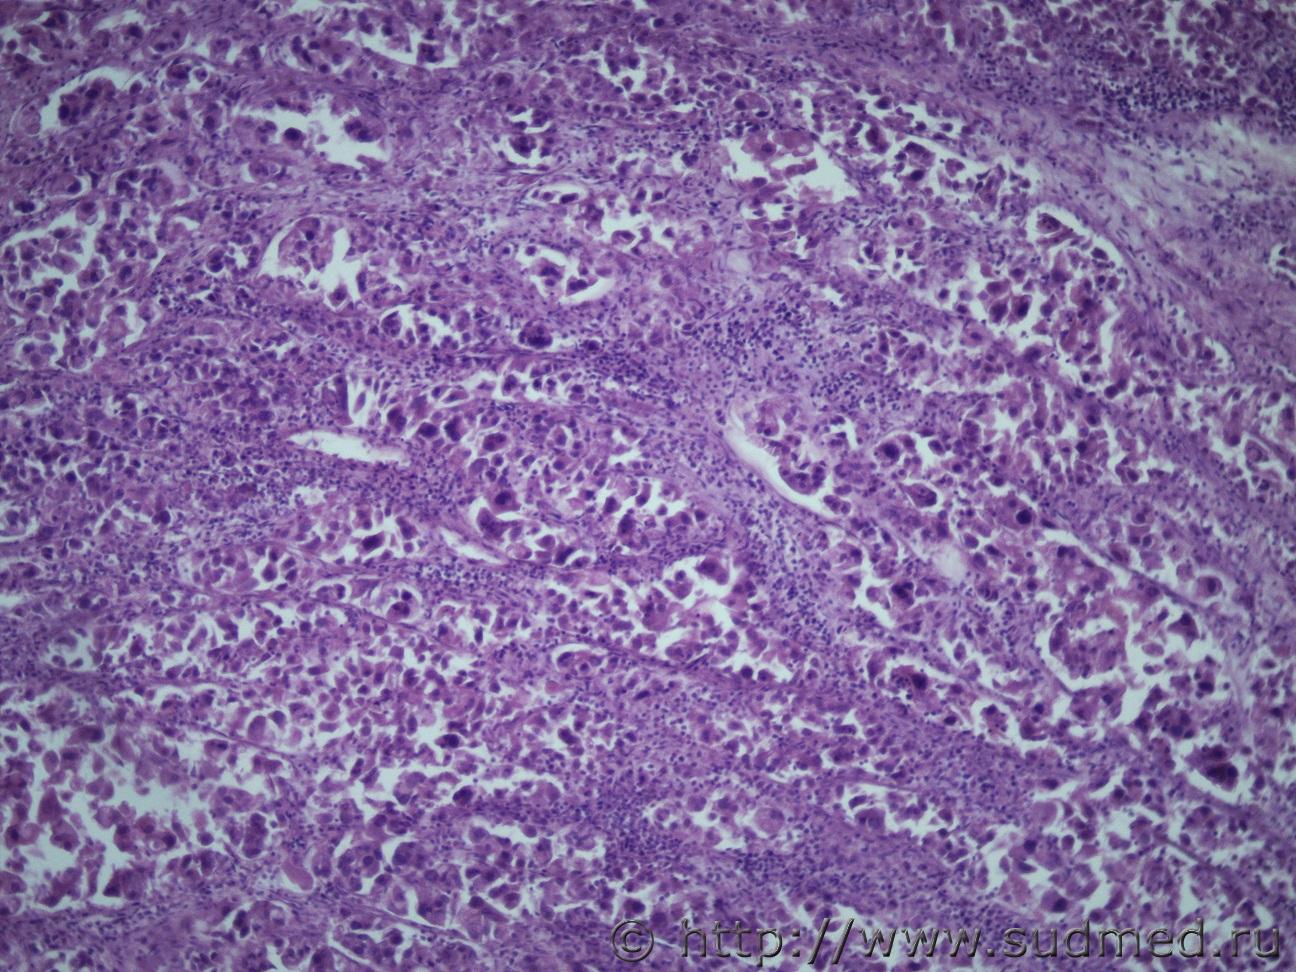

Ув. коллеги нужна помощь. Муж 60 лет. Эксперт присылает злокачественное новообразование левой почки с метастазами в правую почку и легкие. В стеклах опухоль в почке над капсулой (какая это почка правая или левая не указано) Судебная медицина - Прикрепленное изображение Судебная медицина - Прикрепленное изображениеСудебная медицина - Прикрепленное изображениеСудебная медицина - Прикрепленное изображениеСудебная медицина - Прикрепленное изображение

По мне - железистый вариант гипернефроидного рака.

Гипернефроидный рак.

Почечно медуллярная карцинома с mts в легкие